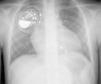

A seven-year-old girl was diagnosed with transposition of the great arteries with ventricular septal defect and pulmonary stenosis. In the neonatal period, a modified Blalock-Taussig shunt was performed, and at the age of six a Rastelli procedure. Postoperatively she required a permanent VVIR pacemaker (Microny II SR, St. Jude Medical, IsoFlex lead) due to irreversible complete AV block. One year after surgery, she was admitted to the Emergency Department due to pectoral stimulation by the pacemaker. Assessment revealed intermittent ventricular stimulation thresholds (variable and above 2.4V), with unchanged lead impedance. The patient presented advanced AV block. A surgical revision was performed and the pacing lead was extracted by manual traction. There was no macroscopic evidence of lead fracture. A new pacemaker system was inserted (Identity ADx VDR, St. Jude Medical, AV Plus Dx lead), through the right subclavian vein. P and R wave amplitudes were 2mV and 7.1mV, respectively, and the ventricular threshold was 0.75V. The final image showed the pacing lead to be correctly positioned (Figure 1).